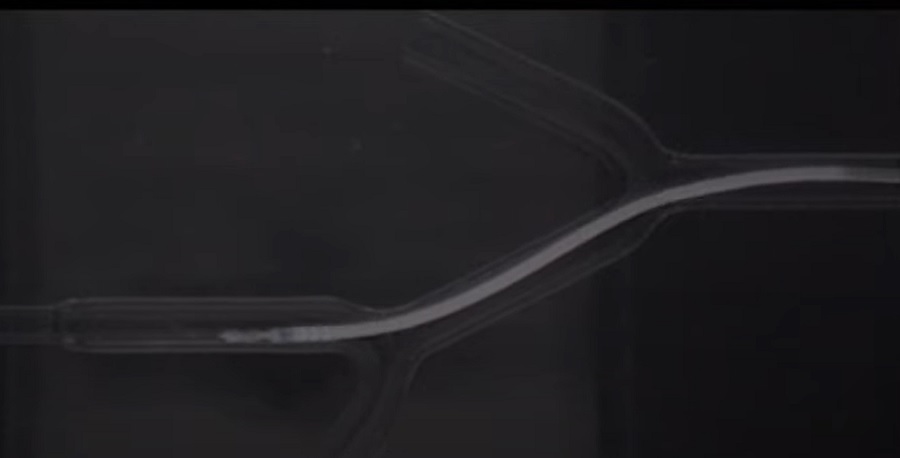

A robot befecskendezésére katétert használnak, ezen keresztül jut a kezelési terület közelében lévő véredénybe. A külső mágneses mező pedig forgó mozgás létrehozására szolgál, hogy a robot le legyen kötve a katéterről. Ezután a külső mágneses mező segítségével a robot a kezelési helyre irányítja a navigációt, 3D-s térképre támaszkodva.

Amint a robot az artéria vagy a véredény kezelést igénylő részére érkezik, számos feladatot tud végrehajtani - beleértve a ballonozást, a vérrögök felszívását és a kontrasztfesték vagy gyógyszerek lokalizált bejuttatását. A feladat befejezését követően a külső mágneses rendszer visszavezeti a robotot a katéterhez, majd eltávolítják azt a testből.

A kutatók tanulmányukban először egy víztartályban úszó mesterséges véredényben tesztelték a technikát, ami sikeresnek bizonyult. Ezután kismalacok felületes combcsont artériáiban, altatásban tették próbára robotjukat.